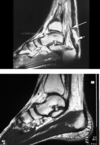

C'est quoi ça?

32